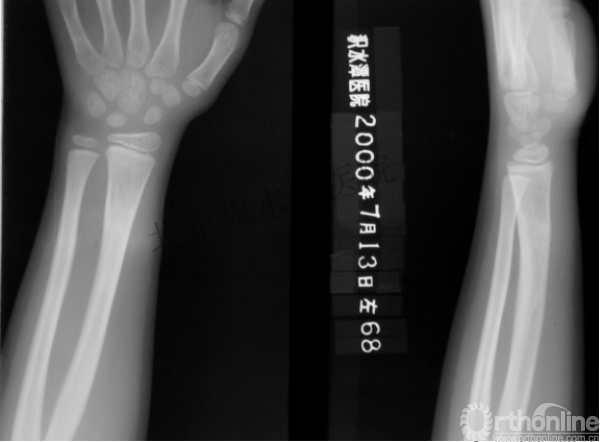

闭合复位再固定加尾帽

又过了4年!时间来到2015年

一年以后顺利愈合,实则危机四伏

数月后再骨折!牵引!

髋人字支具

外固定架术后一年

整整11年!是否治疗终结?